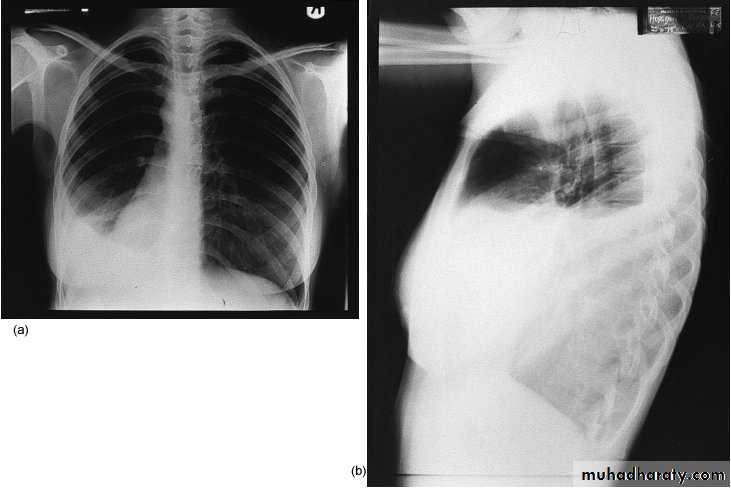

1-Thoracostomy(chest tube )In pnemothorax at 5nd ICS ant. axillary line

2-Mediastenial vertical incision used for cardiac op

3-Intercostals at 5th ICS & 8th ICS

4-Thoracoabdominal extended to Rt or Lt paramedian used for oesophagial op

-- some use valve for one way direction as in chest tube use underwater seal because plural cavity pressure less than atmospherec pressure ,